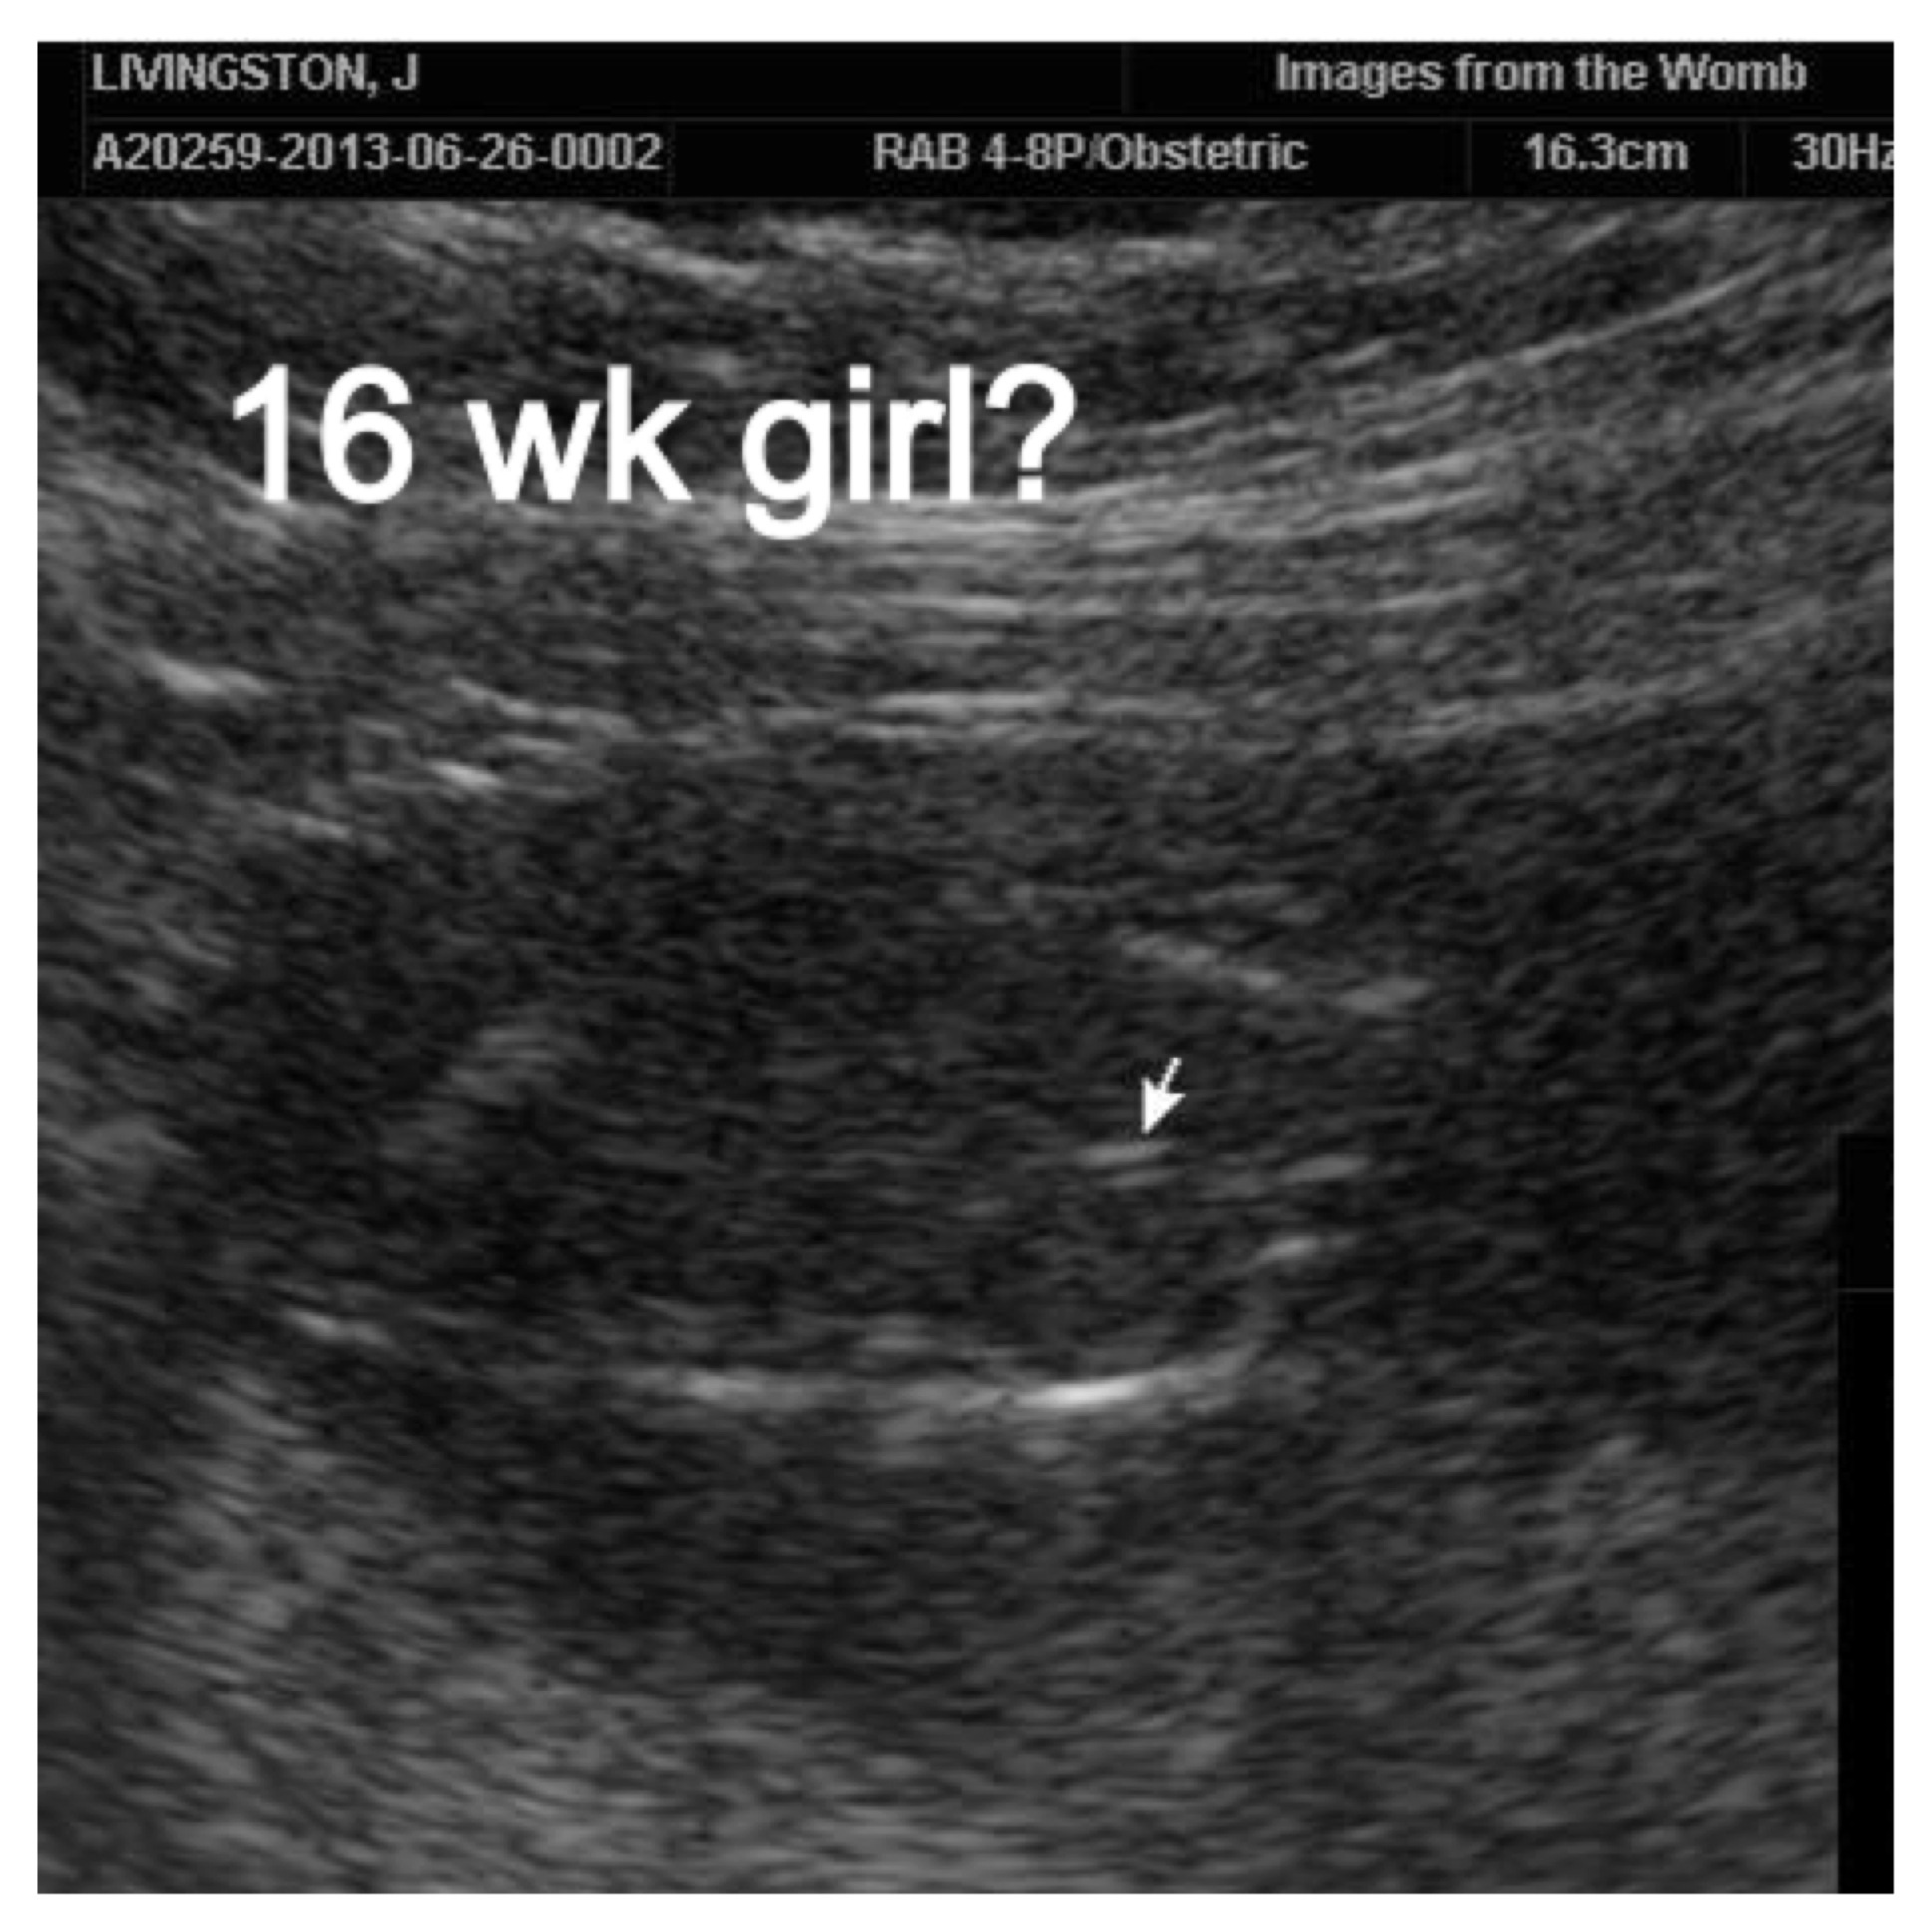

That 16 week pic is such bad quality! ... It def looks like a boy at 20 weeks tho

Either was fine. Hearing a girl though was amazing and to be told four weeks later was a boy - huge shocker. I don't know if I'm in denial or what but I cannot clearly see a boy part. I mean I don't even see legs in the bottom shot.

Plus the part the arrow is pointing to is very pointy. Every uS I've seen it's rounded.

Can`t really tell on the 16 week scan, but the 20 week looks like a boy .

Very bad quality pics.

I would maybe get another ultrasound done if you can. It is so hard to tell in either picture. On the top one I can't really make out anything and on the bottom I don't see anything else around what could possible be the boy part. Fingers crossed you get a good shot!

I agree on getting another ultrasound! I don't see anything on the 16 week but what I see on the 20 week doesn't scream boy to me. Both my boys were VERY obvious at 20 weeks. Hope you get your DG!

The 20 week ultrasound pic looks clearly like a boy to me! I cant see much of anything in the 16 week scan sorry :/ How frustrating for you!!